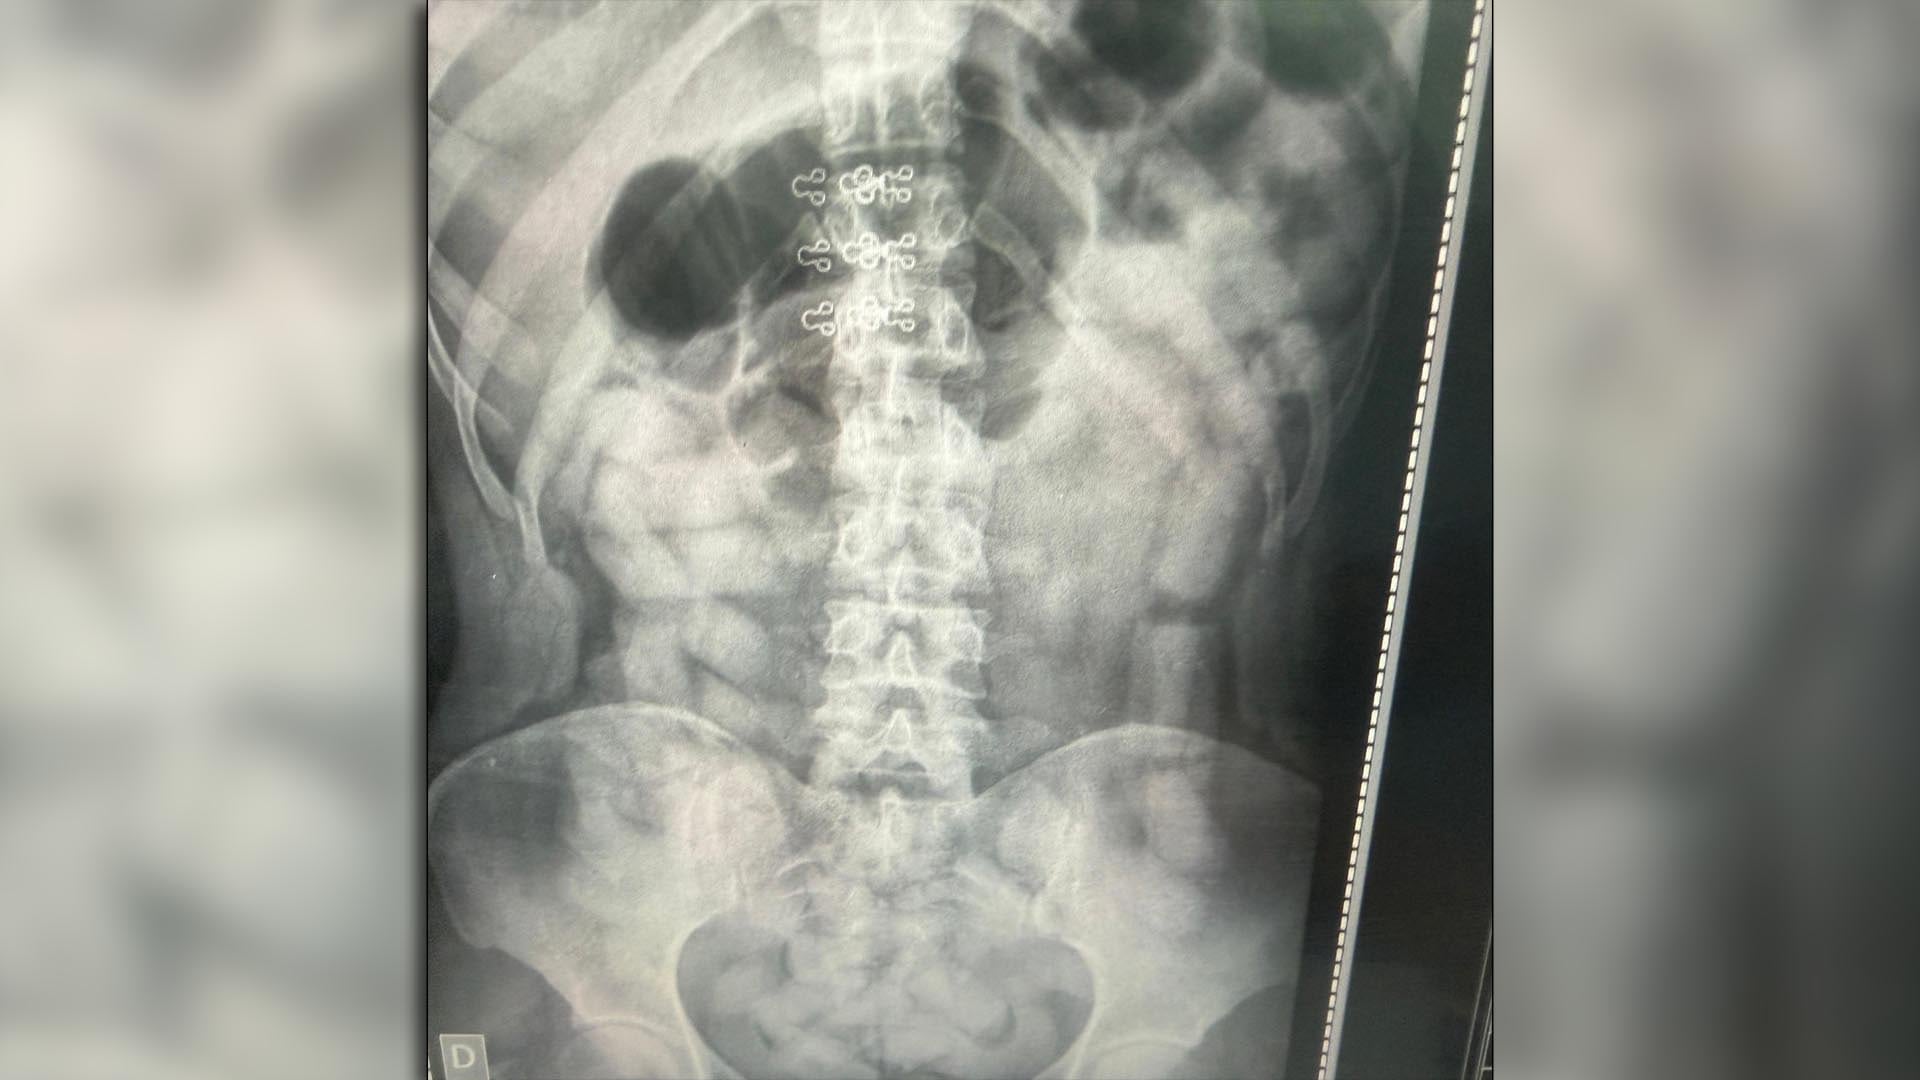

Al día siguiente, la hipótesis sobre la modalidad de “mulas” llevó a que todos los pasajeros se sometieran a placas radiográficas. Las imágenes mostraron la presencia de cuerpos extraños en el abdomen de cuatro mujeres y dos hombres, ilustrando la peligrosidad de este método para la salud.

Los seis pasajeros identificados fueron internados bajo custodia en los hospitales de Santa Ana y Los Sarmientos, donde expulsaron en total 503 cápsulas que superaron los 6 kilos de cocaína. El área de Criminalística y Estudios Forenses contabilizó 752 cápsulas con un peso total de 10 kilos 316 gramos.